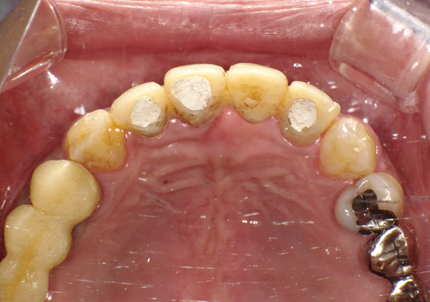

18.インプラント埋入後 パノラマレントゲン

19.アバットメント装着(2020年1月)

ISQ値 右上2 (71) 左上1 (73) 左上2 (72)